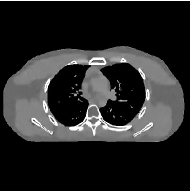

This section compares the reconstruction quality and runtime among the proposed MBIR method, PWLS-ST-, and other three MBIR methods, PWLS-EP, PWLS-DL, and PWLS-ST-. Table I shows that, for both 2D and 3D sparse-view CT reconstructions of the XCAT phantom, the proposed PWLS-ST- model outperforms PWLS-EP and PWLS-ST- in terms of RMSE. In addition, PWLS-ST- using a square transform (of size ) achieves lower RMSE than PWLS-DL using an overcomplete dictionary (of size ) for 2D sparse-view reconstructions. Fig. 3(a) and Fig. 4 show the reconstructed images for 2D and 3D phantom experiments, with different reconstruction models and different number of views. (See the corresponding error maps in the supplement.) The proposed PWLS-ST- consistently gives more accurate image reconstructions compared to other MBIR methods. Specifically, PWLS-ST- has smaller errors in the heart region (see zoom-ins in Fig. 3(a)) of 2D reconstructions than PWLS-DL and PWLS-ST-. In addition, compared to PWLS-ST-, PWLS-DL and PWLS-ST- have some ringing artifacts around the edges with high transition, e.g., edges between air and soft tissues. (See a comparison of profiles of PWLS-ST- and PWLS-ST- in the supplement.) In particular, PWLS-ST- and PWLS-DL give more visible ringing artifacts for 2D reconstruction from fewer views, and PWLS-ST- has these ringing artifacts for 3D reconstructions regardless of the number of views (see zoom-ins in Fig. 4). Table II reports runtimes of different MBIR methods in reconstructing the -views XCAT phantom scan. (FBPConvNet is a non-MBIR method and its runtime for processing a image is approximately one second with a TITAN Xp GPU.) While providing better reconstruction quality, the proposed Algorithm 1 of PWLS-ST- has shorter runtime compared to the algorithms of PWLS-DL and PWLS-ST- in Section III-A. Similar to the PWLS-EP algorithm, the reconstruction time of the PWLS-DL, PWLS-ST-, and PWLS-ST- algorithms can be further reduced by using ordered subsets [51].

![]() |

| (b) 3D axial cone-beam CT experiments |